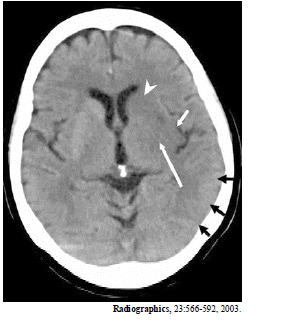

Enunciado 542712-1

A imagem acima é de uma paciente de 65 anos de idade, com hemiplegia direita há cinco horas. Com base nessa imagem, é correto afirmar que

a cabeça de flexa indica o núcleo caudado.

Enunciado 542711-1

as flechas negras indicam edema cortical no lobo occipital.